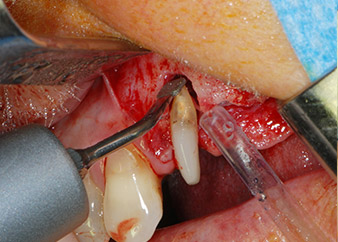

One month later, on the day of surgery, pain and inflammation at tooth 24 were minimal, but mobility of Miller class 2 was still present. After opening the flaps and cleaning the periapical and peri radicular infected tissue, the extent of the bone defect became obvious (Figs. 2 and 3).

At the buccal root, all vestibular and distal bone was missing. Attachment was essentially restricted to the palatal root, underlining the preliminary poor prognosis. Tooth 27 also showed a reduced horizontal attachment and a minimal apical rarefaction (cf. Fig. 1) without clinical symptoms.

total loss of bone and attachment

Fig. 2 and 3: After raising flaps, one month after endodontic revision and initiation of full-mouth periodontal therapy, the buccal root of tooth 24 showed a total loss of bone and attachment.

However, we maintained our initial plan to retain both teeth as temporary bridge abutments during the six-months osseointegration period of the implants. At reentry, the situation would have to be reassessed. First, in an attempt to manage the endo-perio problem, the remaining root surface was carefully debrided with piezoelectric equipment (Piezomed, W&H, used with the spatula-shaped insert S1, originally designed for erosion of the lateral sinus wall) (Fig. 4).